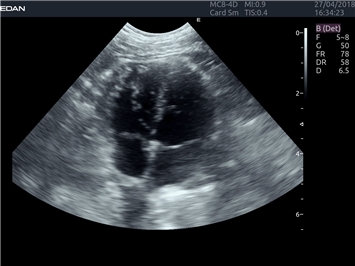

EDAN Acclarix LX4 VET

EDAN Acclarix LX4 VET представляет собой профессиональную ультразвуковую систему, специально разработанную для ветеринарных исследований. Сочетание стабильности, высокой производительности и эффективности делает эту систему идеальным выбором для современной ветеринарной практики.

M-режим:

Да

B-режим, Двухмерное сканирование: